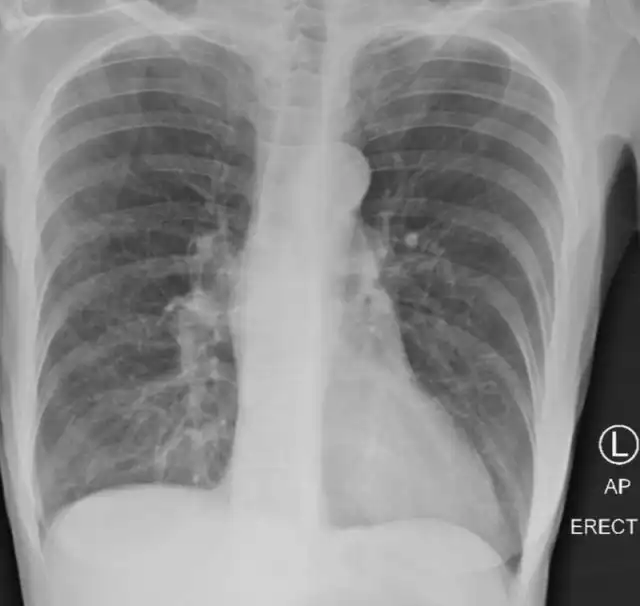

Так выглядят лёгкие здорового человека. Чёрные области - это воздух.

Это лёгкие курильщика.

А это - лёгкие человека, переболевшего COVID-19

Как рассказала доктор изданию NewsNationNow, белая "паутина" на снимке - это оставшиеся рубцы на лёгких. Невооруженным взглядом видно, что легкие после коронавируса выглядят намного хуже, чем легкие курильщиков. По словам врача, после COVID-19 отдышка сохраняется на долгое время, а также не исчезает риск появления тромбов и возникновения пневмоторакса.